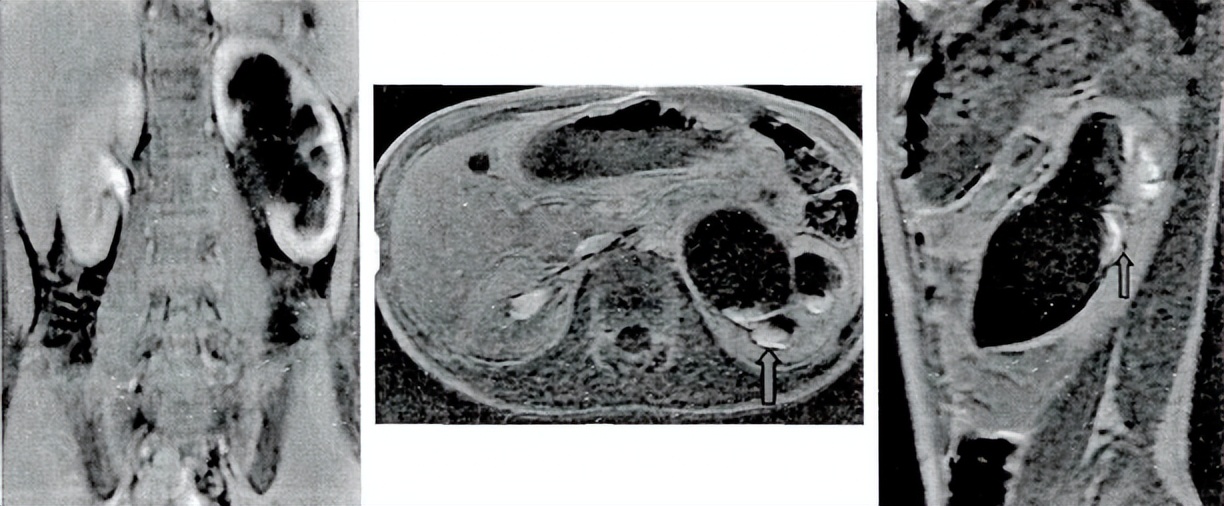

a b

C d

男孩,7月,双侧先天性肾积水。B超示左侧APD21MM,肾盏扩张18*10MM,右侧APD25MM,肾盏扩张20*10MM。

a:D重建水成像,右侧肾盂中度扩张,左侧肾盂轻度扩张,且右侧可见肾盂输尿管连接处扭曲狭窄。

B:DRS结果中示双侧肾脏均对速尿无反应,双侧排泄曲线未见明显下降趋势,分肾功能L:47%,R:53%。

c:动态增强Ti皮质期扫描,右侧肾盂分离程度及肾皮质变薄程度都较左侧重。

D:肾盂排泄曲线示左侧较右侧平坦,右侧PTT>1.5Min,左侧RTT=11.4Miii.LMRU测得双测分肾功能为L:54%,R:46%.综上结果予行腹腔镜下右侧肾盂成形术,术后3月B超随访示右侧APDMMM,无肾盏扩张,左侧APD13MM,无肾盏扩张,均较术前减轻。

男孩,2月,双侧先天性肾积水。B超示左侧APD22MM,肾盏扩张15*12MM,肾实质.4-4.8MM;右侧APD25MM,肾盏扩张16*18MM,肾实质1.9-4.9MM。

a:3D重建水成像,双侧肾盂均重度扩张,双侧未见明显输尿管形态。

B:DRS结果中示双侧肾脏均对速尿无反应,双侧排泄曲线未见明显下降趋势,左侧分肾功能为46%,右侧为54%。

c:动态增强Ti皮质期扫描,双侧肾盂重度分离,双侧肾皮质重度变薄。

D:肾盂排泄曲线示双侧均斜向上呈梗阻曲线,双侧RTT>15Min。fMRU测得双测分肾功能为L:42%,R:58%.综上结果予双侧肾盂成形术及左肾造瘘术,手术顺利,术后2月复查B超示肾盂积水程度较前减轻由SfUiv降至ii级。